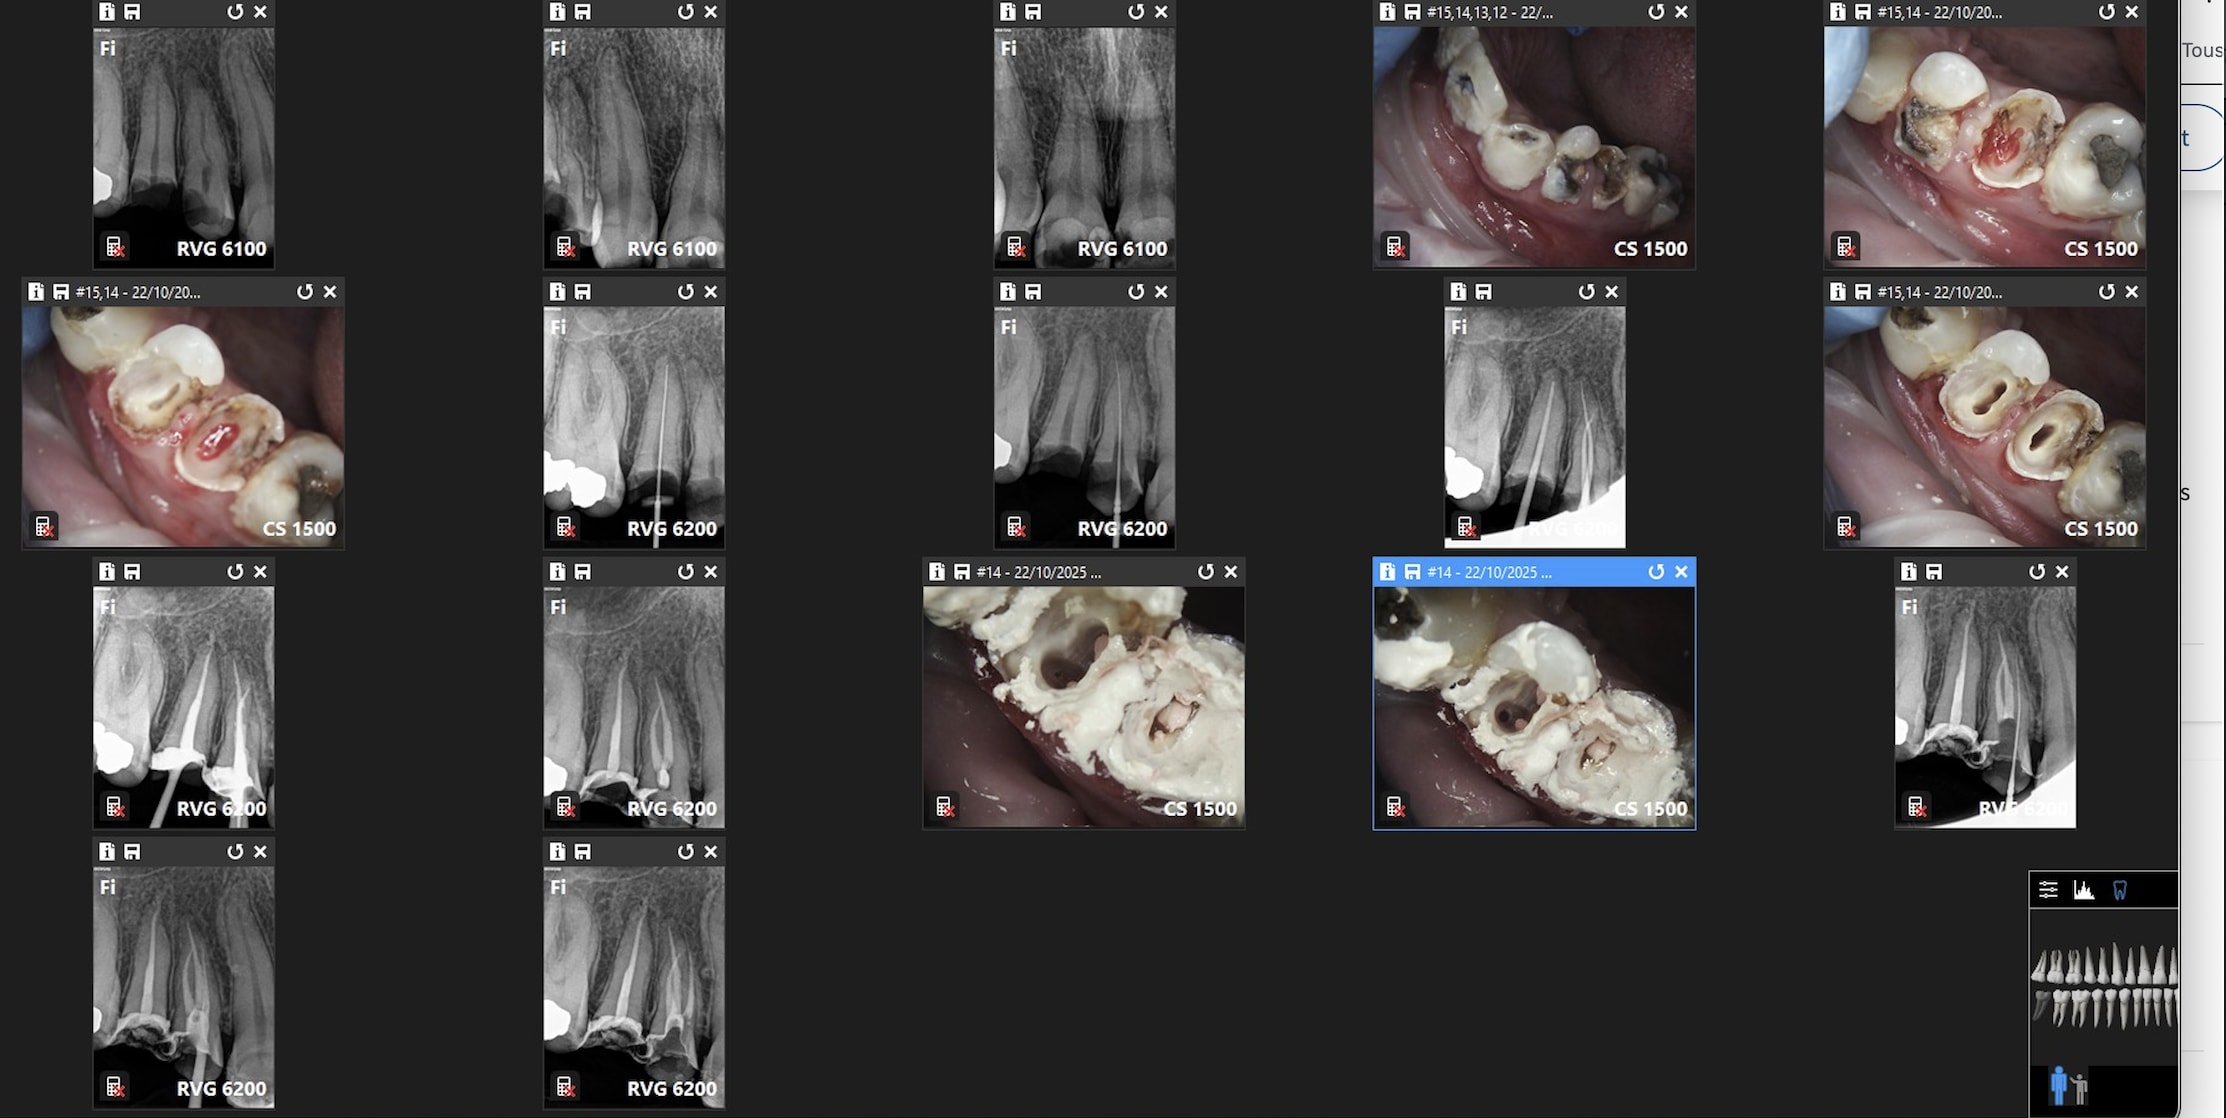

Comparaison des traitements de 2 praticiens différents au même tarif. Même patient 16 26. Pourquoi se faire chier aucun souci sur 26. ,

> Comparaison des traitements de 2 praticiens différents au même tarif. Même

> patient 16 26. Pourquoi se faire chier aucun souci sur 26. ,

c est terrible parce que selon Gabzou... le gars qui a foiré l endo 26 a fait exprès puisque c est facile...

si c était si facile, tout le monde le ferait.

> > Comparaison des traitements de 2 praticiens différents au même tarif. Même

> > patient 16 26. Pourquoi se faire chier aucun souci sur 26. ,

> c est terrible parce que selon Gabzou... le gars qui a foiré l endo 26 a fait

> exprès puisque c est facile...

> si c était si facile, tout le monde le ferait.

Il y a un nouveau concept : c'est pas que ce soit facile c'est qu'il s'en foutent. Tu me diras au tarif sécu rien d'étonnant. Vas trouver une assistante ou n'importe quel salarié qui va faire consciencieusement des heures sup non payées parce qu'elle le vaut bien. je prends une heure 30 par molaire et 1H pour les autres endos ( avec reconstitution ) contre 1H et 30 mn avant. Bien sur j'arrive à le faire en moins de temps la plupart du temps mais si je ne prends pas le temps qu'il faut, ce boulot que tu apprends à aimer ( c'est pas inné au départ ) se transforme en corvée. Un autre nouveau concept élaboré aussi par un de nos confrères, salarié du contrôle dentaire, c'est que la justification du tarif indigent des endos est que on se "rattrape" sur la couronne qui va dessus, de là à penser qu'on dévitalise pour faire des couronnes il n'y a qu'un pas qui est franchi allègrement par certains . Du coup je me mets à faire des couronnes sur dents vivantes ce que je ne faisais jamais avant , on fait une endo parce qu'on a peur qu'il y ait des sensibilités ou une nécrose après pas pour poser l'indication d'une couronne pour délabrer une dent qui l'est déjà. Une endo facile c'est comme une extraction facile a priori ca n'existe pas tu peux dire que c'est facile ou difficile une fois que tu l'as faite. Le plus souvent c'est facile.

rien a redire sur les endos de chicot

neanmoins la question de gabzou concernant le % de cas réellement difficiles est intéressante car chicot tu illustres ce propos par des cas que tu dois trouver emblématiques datant de 2019/2020

Indépendamment du reste, il y a clairement une racine MV non traitée dont on distingue le canal, ce qui est l'anatomie standard d'une 26.

Conclusion, le praticien l'a sciemment ignorée pour aller plus vite.

On peut discuter de la rémunération, des raisons qui ont amené ce praticien à choisir de bâcler le travail, mais il est indiscutable que le praticien ne peut pas avoir ignoré avoir fait n'importe quoi.

J'ai bien précisé que tout n'est pas facile. Cette 26 l'est, je n'ai quasiment aucun doute.